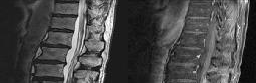

Preoperative MRI images are shown from a 67-year-old woman with neck pain, bilateral upper extremity paresthesias, progressively worsening balance, several falls, and increasing problems in both hands with dropping objects. Figure 1 is a sagittal view, Figure 2 is an axial cut at C2-3, Figure 3 is an axial cut at C5-6, and Figure 4 is an axial cut at C6-7. The patient’s motor strength is grade 4+ of 5 in the bilateral upper extremities.

What is the best next step?

4. Posterior decompression and fusion Discussion: D

The patient has degenerative changes with central and foraminal stenosis from C2-7, including spinal cord compression at C2-3, C5-6, and C6-7. Her progressively worsening balance, falls, and clumsiness are consistent with cervical spondylotic myelopathy. Given the progressive nature of the neurologic symptoms, surgery is recommended for patients with worsening

symptoms. Physical therapy potentially could provide pain relief but would not address the spinal cord compression. Cervical epidural steroid injection is not recommended because of the increased neurologic risk in the setting of substantial spinal cord compression. Given the multiple levels involved and the extension to the C2-3 level, an anterior approach would increase the risk of morbidity and pseudarthrosis compared with the posterior approach, which would allow adequate decompression of the central and foraminal stenosis.

Surgery for cervical myelopathy is performed to decompress the spinal cord, stabilize the spine, and prevent further neurologic injury. Most patients obtain considerable pain relief and some improvement in balance and clumsiness, depending on the severity of the symptoms. Complete resolution of all symptoms should not be expected.